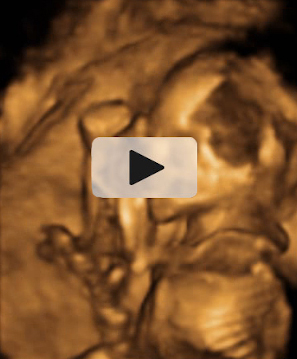

En la imagen ecográfica podemos ver el corte de la cabeza fetal donde se muestra la medición de un ventrículo cerebral aumentado de tamaño (o ventriculomegalia).

Ecografía Embarazo 2D y 3D Semana 20 - MALFORMACIONES FETALES

Ecografía Embarazo 4D Semana 20 - MALFORMACIONES FETALES